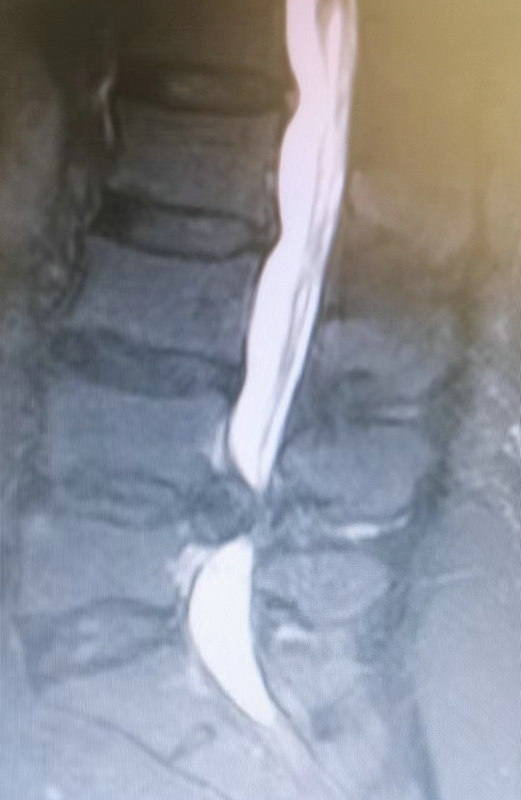

患者王某某,女,49歲,該患者5年無明顯誘因出現(xiàn)腰部疼痛伴左下肢放射痛、麻木不適,予以針灸、理療等對癥治療,病情時(shí)輕時(shí)重。3月前勞累后再次出現(xiàn)上述癥狀,且癥狀進(jìn)行性加重,嚴(yán)重影響生活,聽村民介紹后到市二院骨傷科三病區(qū)就診。經(jīng)檢查后,腰椎動(dòng)力位片提示腰椎不穩(wěn);腰椎核磁提示腰4/5椎間盤巨大突出,腰4/5椎管狹窄。副院長姚雄兵帶領(lǐng)骨三科團(tuán)隊(duì)立即組織病例討論,仔細(xì)詢問病史及體格檢查,結(jié)合影像學(xué)檢查,全面評估后與患者及家屬溝通,確定行“經(jīng)皮脊柱內(nèi)鏡輔助下腰椎椎體間植骨融合內(nèi)固定(ENDO-PLIF)術(shù)”。手術(shù)邀請甘肅中醫(yī)藥大學(xué)附屬醫(yī)院椎間盤中心主任李元貞指導(dǎo),在手術(shù)麻醉科的配合下術(shù)程順利,術(shù)后患者左下肢放射痛、麻木癥狀完全緩解,手術(shù)效果良好。